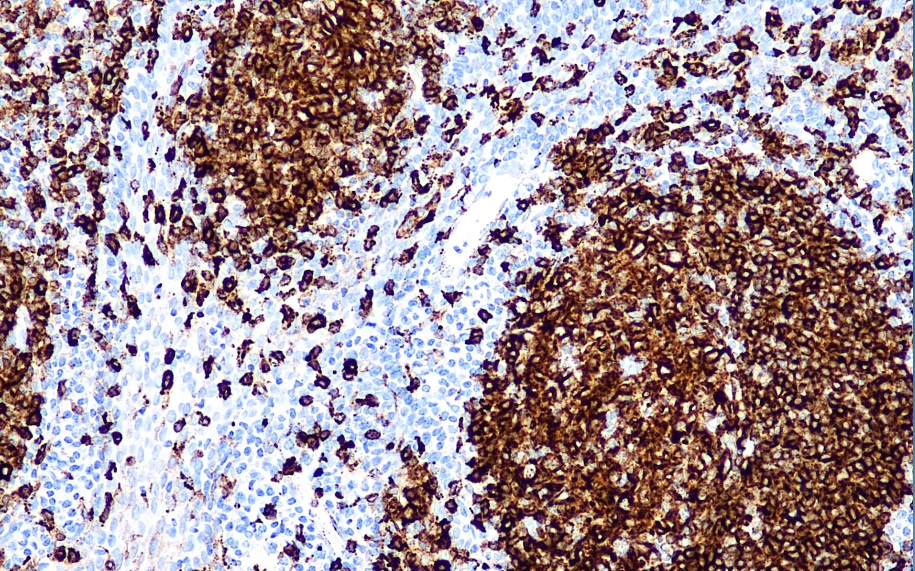

阳性对照: 扁桃体

HLA-DR即人类白细胞抗原Ⅱ类基因中的DR亚区,其编码的蛋白是分子量为29-33kD的双链分子,主要表达于某些免疫细胞表面,如B细胞、单核/巨噬细胞、树突状细胞及活化的T细胞。此抗体可用于淋巴瘤及白血病的分型。

HLA-DR抗体试剂可与HLA-DR分子抗原特异性结合,含HLA-DR抗体试剂的免疫组化试剂盒适用于淋巴瘤及白血病的精准诊断。